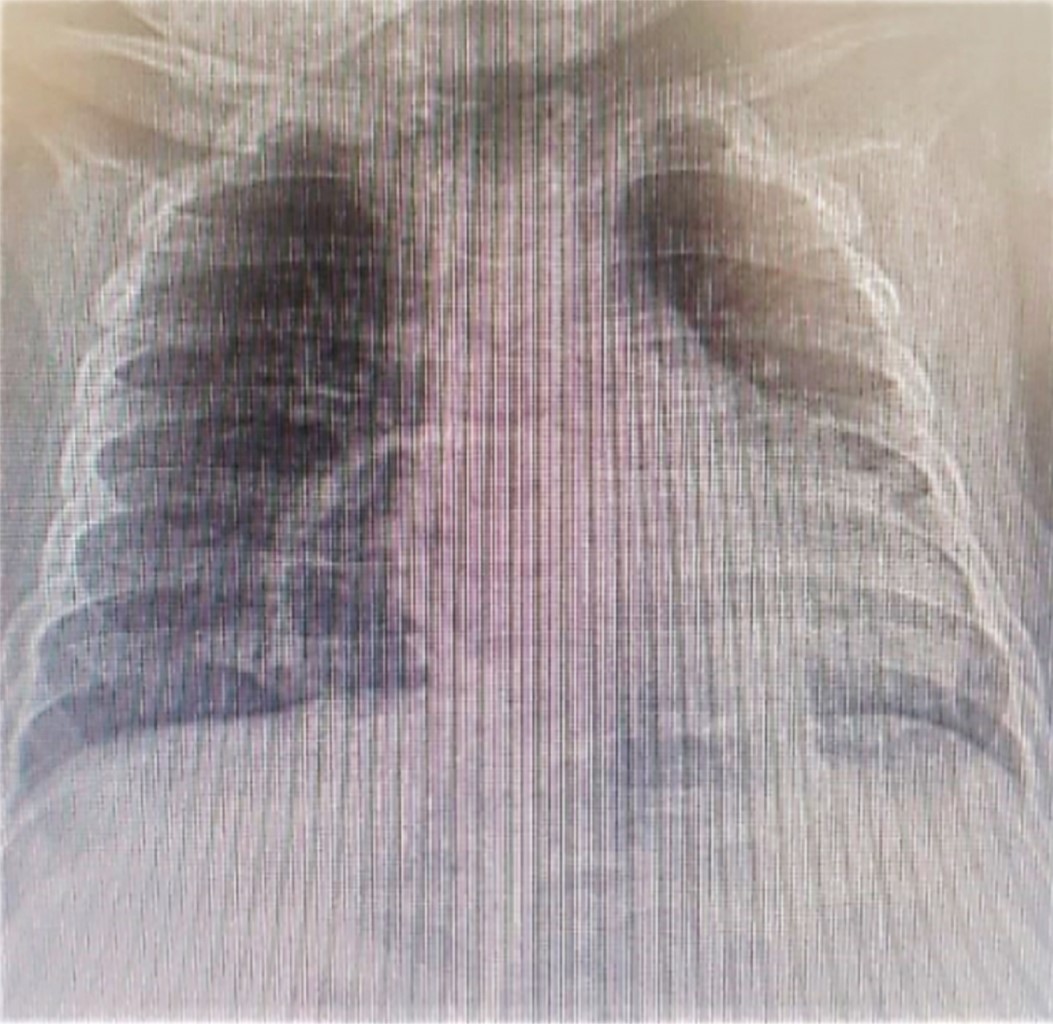

Paciente femenino de 13 meses, originaria y residente de Bogotá, Colombia. El abuelo paterno con diagnóstico de síndrome de Down. Ingresó en compañía de su madre, quien refirió un cuadro clínico de siete días de evolución caracterizado por tos productiva, no emetizante, no cianosante, acompañada de rinorrea hialina y fiebre de 38 oC. Acudió a urgencias de un centro de salud de primer nivel de atención, donde la encuentran con desaturación y aumento de trabajo respiratorio, por lo que indican oxígeno suplementario. Se sospechó neumonía. En biometría hemática se evidencia leucocitosis con neutrofilia, así como anemia microcítica hipocrómica. En Rx de tórax se observó imagen redondeada radiolúcida, con borde radiopaco bien delimitado, lo cual se identificó como hernia diafragmática anterior. Se inició tratamiento con penicilina cristalina. Dado que la paciente presenta deterioro clínico, se decide trasladarla a un centro de salud de mayor complejidad.

En el examen físico a su ingreso a la institución especializada, se encontró en buenas condiciones generales, peso de 10.2 kg, talla de 76 cm, con estado nutricional normal (acorde a las curvas de crecimiento para niños con síndrome de Down), con dificultad respiratoria leve, desaturación que se corregía con oxigenoterapia a bajo flujo. En la exploración del tórax se detectó presencia de crépitos finos en ambas bases pulmonares. Al revisar la Rx de tórax se corrobora diagnóstico de hernia diafragmática, pero sin datos de neumonía.

Al segundo día de ingreso, el servicio de Cirugía Pediátrica confirma que la hernia diafragmática anterior (Figuras 1 y 2) es de tipo HM, y consideran manejo quirúrgico. Al tercer día se corrige por laparoscopía, sin complicaciones. La evolución postquirúrgica fue favorable.

Figura 1